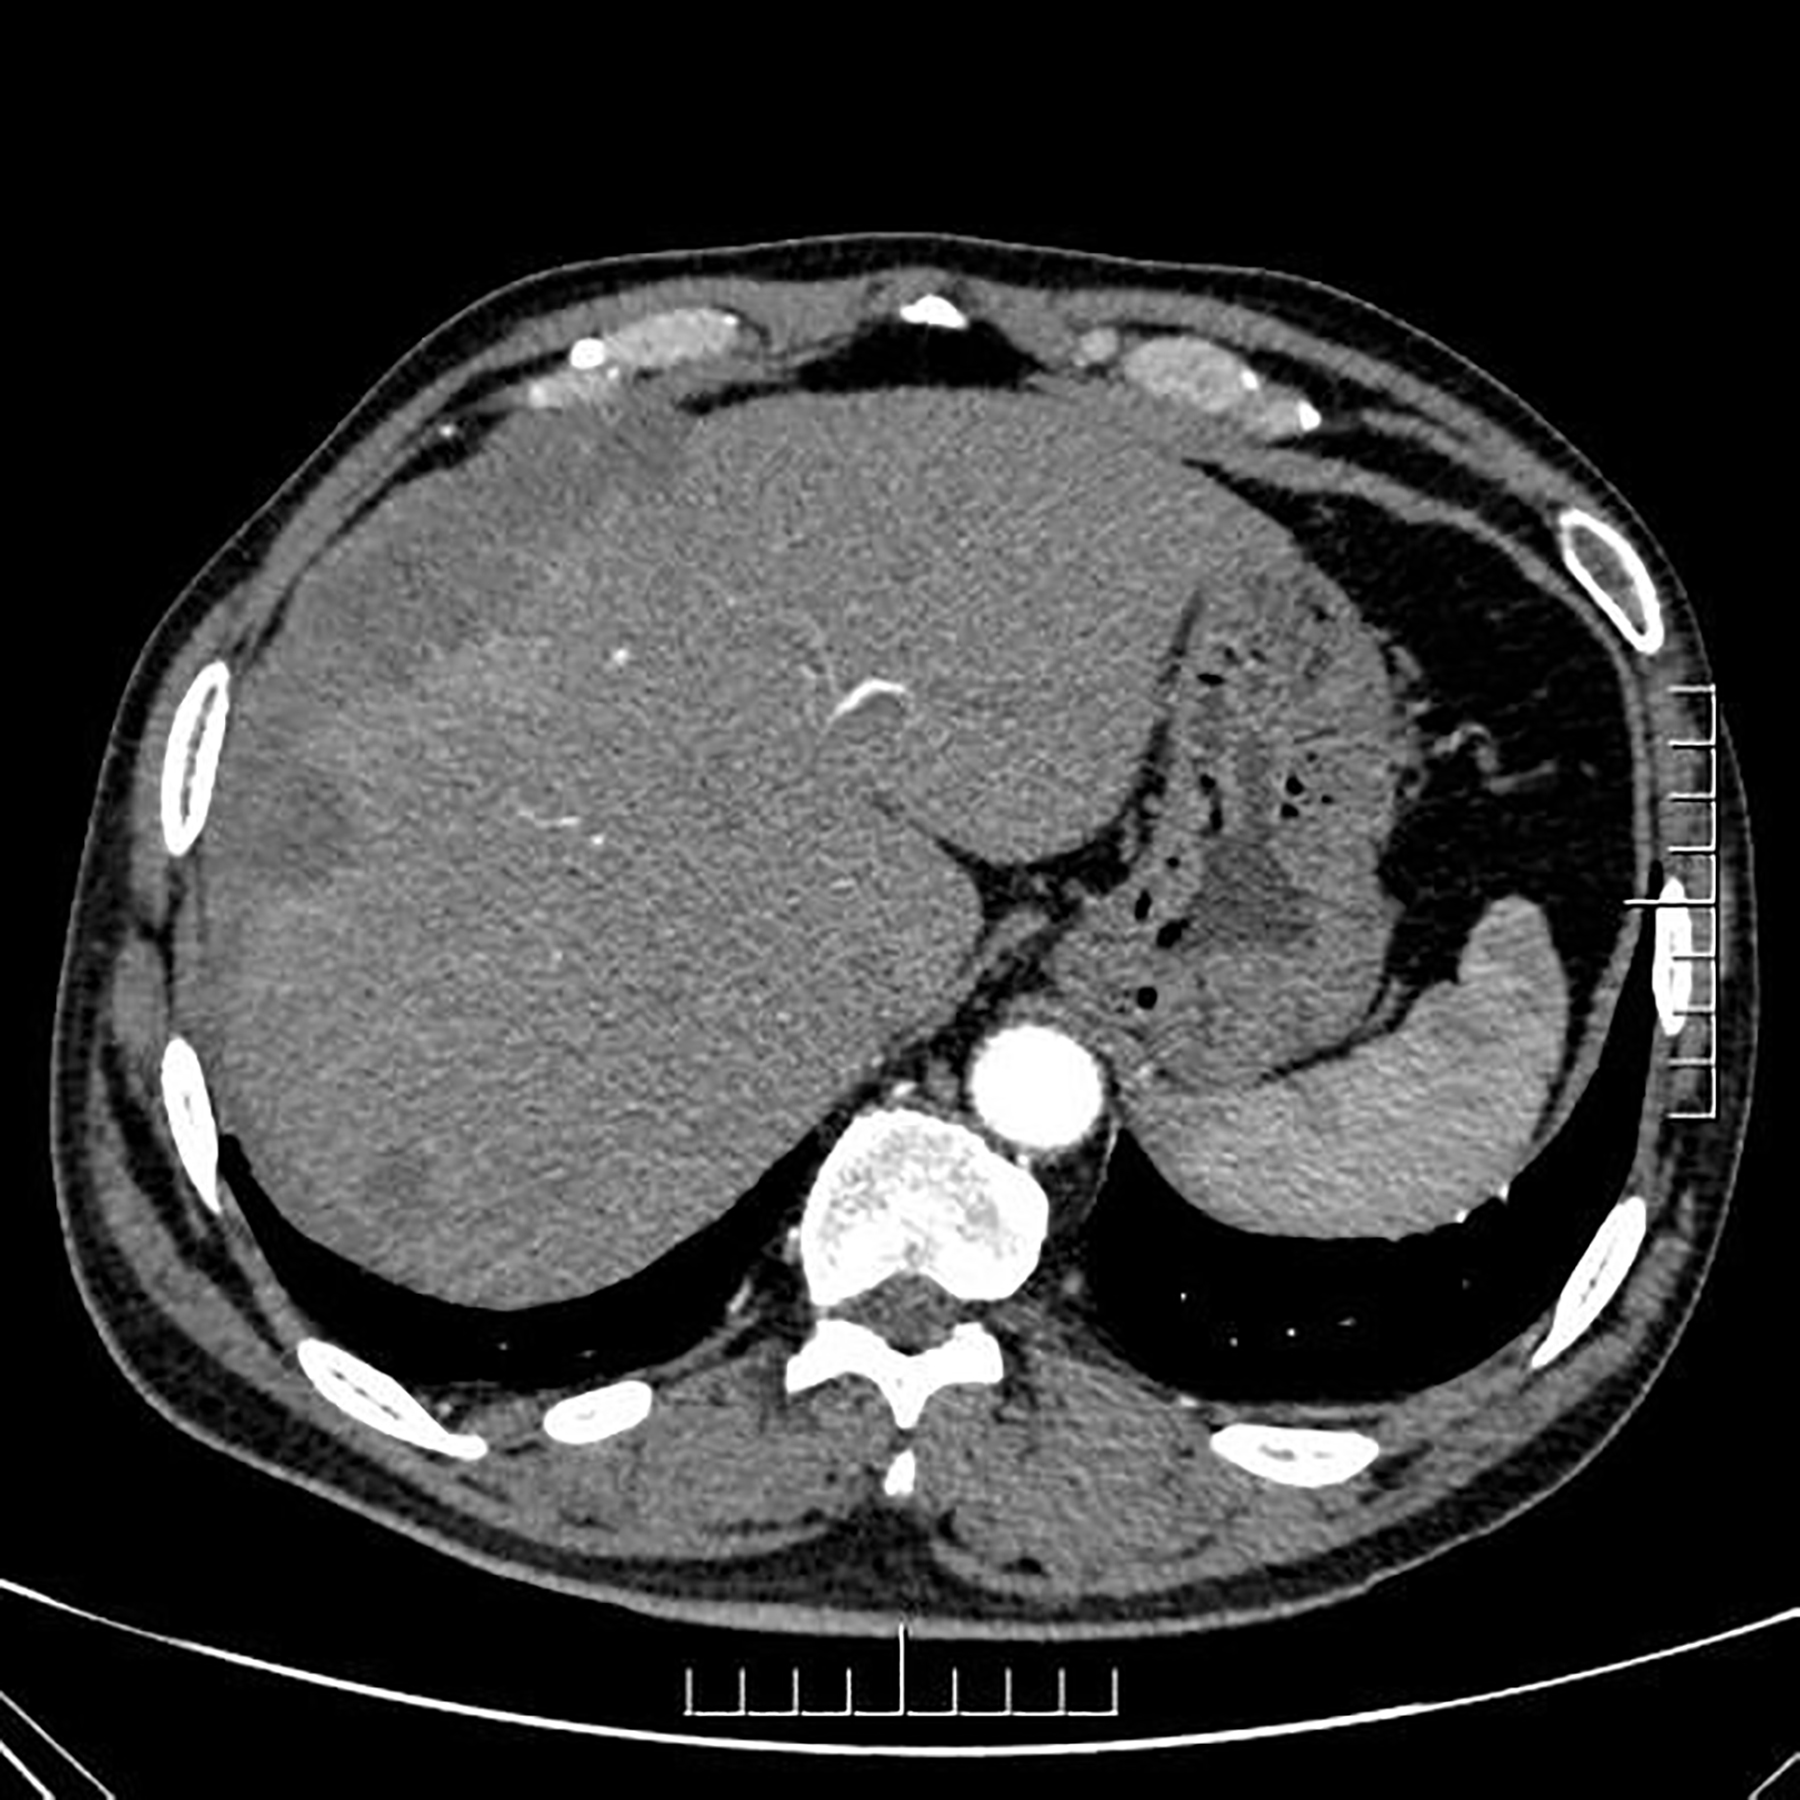

Figure 1

Axial contrast-enhanced CT image of the abdomen during the late arterial phase showing multiple nodular and sheet-like low-attenuation lesions with peripheral enhancement in the right subdiaphragm and right anterior and left medial lobe of the liver.

Ultrasound (US) imaging revealed an ill-defined, heterogeneous, hypoechoic lesion involving the right subdiaphragm as well as the right anterior and left medial lobes of the liver. The hepatic parenchyma showed diffuse heterogeneity without distinct nodules. Thoracic computed tomography (CT) scans demonstrated an elevated right diaphragm, bilateral pleural thickening, and bilateral diaphragmatic pleural calcifications, along with enlarged anterior mediastinal lymph nodes. No significant pulmonary masses were identified. Abdominal contrast-enhanced CT images in the late arterial phase revealed multiple nodular and sheet-like low-attenuation lesions with peripheral enhancement in the right subdiaphragm, right anterior, and left medial lobes of the liver (Figure 1). These lesions showed “washout” in the portal vein and late phases. Enhanced nodules were observed in the peritoneum around the liver and in the fat septa of the ascending colon. Based on thoracic CT findings, the common primary malignancies were excluded, including masses in the lung, pancreas, spleen, kidneys, ureters, and prostate. Magnetic resonance (MR) imaging indicated intermediate-to-low intensity lesions on T1-weighted images (T1WI) and central intermediate-to-low intensity with peripheral intermediate-to-high signal intensity on T2-weighted images (T2WI). Diffusion-weighted imaging revealed restricted diffusion (Figure 2). No significant retroperitoneal abnormalities were noted. An 18-fluorodeoxy-glucose positron emission tomography with CT (18F-FDG PET/CT) scan revealed abnormally elevated FDG uptake in the poorly defined low-attenuation lesions in the right subdiaphragm and right anterior and left medial lobes of the liver, with a maximum standardized uptake value (SUVmax) of 11.2. Additional FDG activity was noted in the right peritoneum with irregular nodular thickening (SUVmax 7.7) and multiple hypermetabolic nodules in the right abdominal cavity, the largest of which had an SUVmax of 11.9 (Figure 3). No abnormal FDG uptake was observed in the lungs. An ultrasound-guided biopsy of the right subdiaphragmatic lesion and hepatic mass revealed dense fibrocollarous tissue invasion by atypic tumoral cells with spindle, triangular, or polygonal-shaped and hyperchromatic nuclei, involving both the peritoneum and liver (Figure 4). Immunohistochemical analysis showed these cells were positive for Ki-67 (20%), cytokeratin (CK) 7, WT-1, vimentin, CK (pan), D2-40 (weakly positive), and calretinin (CR), but negative for villin, CK20, and CDX-2. These findings supported a diagnosis of desmoplastic malignant peritoneal mesothelioma (DMPM). The patient underwent chemotherapy with pemetrexed and cisplatin and was discharged after completing the treatment.